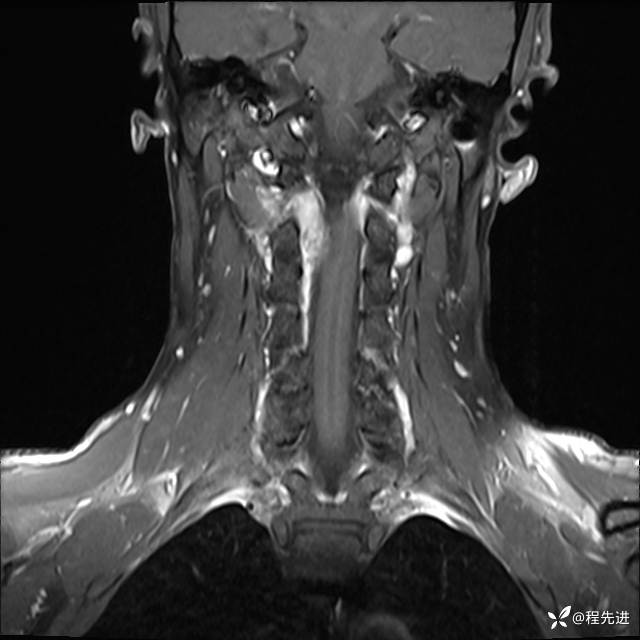

MRI平扫+增强:

T1增强: